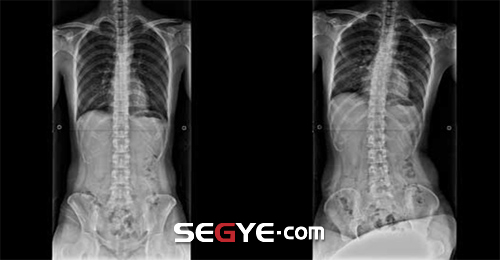

30일 의료계에 따르면 체형질환은 장기간에 걸친 자세습관으로 나타나는 경우가 많은데, 이 중 다리를 꼬는 습관은 바르지 못한 자세습관의 대표격으로, 한 쪽 다리를 꼬게 되면 몸의 중심이 변화하게 되면서 골반이 한 쪽으로 틀어지고 척추는 그 반대 방향으로 이동하여 몸의 좌우를 비대칭으로 변화시킨다.

문제는 이러한 자세가 어느 한 순간 잠시 동안에 유지되는 것이 아닌 습관적인 자세로 굳어질 경우에 있다. 대부분 양 다리를 번갈아 꼬기보다 편하게 여기는 한 쪽 다리만을 꼬는 습관으로 굳어져 있기 때문에, 다리 꼬는 습관은 장기간에 걸쳐 골반틀어짐을 비롯한 기능성 척추측만증 등의 신체불균형을 유발하게 된다.